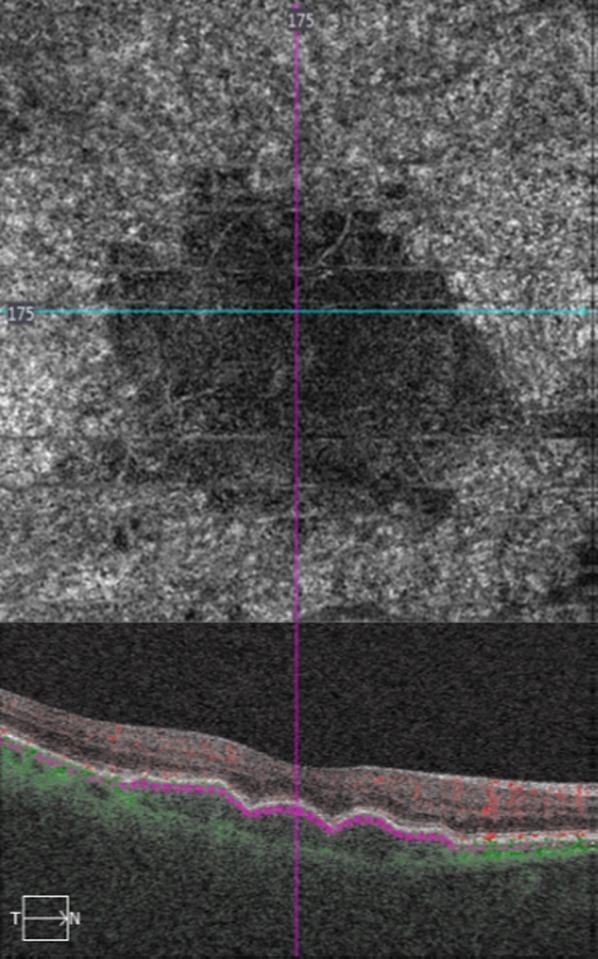

Participants in this study were 36 patients with non-neovascular AMD and drusen. All patients underwent best-corrected visual acuity, slit-lamp examination, spectral domain-optical coherence tomography (SD-OCT), and optical coherence tomography angiography (OCTA).

In all studied cases, the presence of drusen was associated with choriocapillaris' reduced blood flow signal of different extent and severity. Three types of choriocapillaris' non-perfusion were observed, along with an association between the size of drusen and the morphology of choriocapillaris' density defect. Moreover, the extent of choriocapillaris' density change has been related to ellipsoid zone disruption and therefore to visual impairment.

Our study showed that in patients with drusen due to non-neovascular AMD, there is choriocapillaris' impairment of different morphology in OCTA, which is mainly related to the size and location of the drusen.